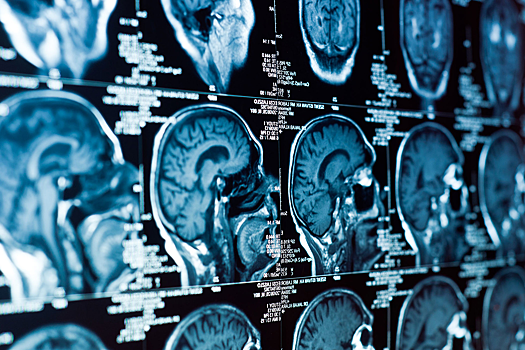

В исследовании участвовали почти 4 миллиона жителей Дании в среднем возрасте 35 лет. За 21 год наблюдений у 16 596 человек диагностировали опухоли центральной нервной системы, включая 4645 случаев менингиомы. Уровень воздействия загрязнителей оценивали с помощью адресных данных и компьютерного моделирования.

Менингиома — это опухоль, растущая из клеток паутинной мозговой оболочки. В большинстве случаев новообразование доброкачественное — оно не прорастает в окружающие ткани и не метастазирует.

После учета возраста, пола, образования и социально-экономического статуса оказалось, что риск менингиомы повышался на 10% при росте концентрации ультрадисперсных частиц на 5747 частиц в кубическом сантиметре.

Увеличение содержания мелкодисперсных частиц PM2,5 в воздухе на четыре микрограмма на кубический метр (мкг/м3) было связано с ростом риска на 21%. При воздействии диоксида азота (8,3 мкг/м3) вероятность развития менингиомы возрастала на 12%.

Связи с более агрессивными опухолями, такими как глиомы, обнаружено не было. Исследователи отмечают, что для подтверждения результатов нужны дополнительные работы. Однако, по словам ученых, улучшение качества воздуха может стать важным шагом в снижении риска опухолей мозга и укреплении здоровья населения.